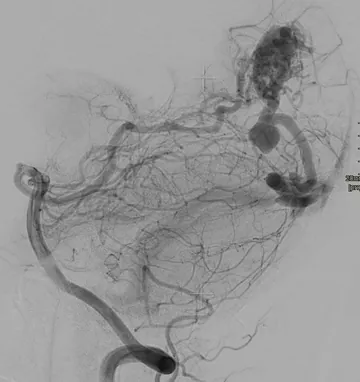

MRI is more sensitive than CT in diagnosing AVMs and provides better information about the exact location of the malformation (fig. 1). MRI uses a powerful magnetic field and radio waves to create detailed images of the brain and other structures. An MRI can provide a clear, detailed view of the brain’s soft tissues, making it particularly useful in imaging AVMs. For even more detailed imaging, a magnetic resonance angiogram (MRA) can be performed, similar to a CTA, a contrast agent is injected into the bloodstream to highlight the blood vessels.

Figure 1: MRI of an AVM.